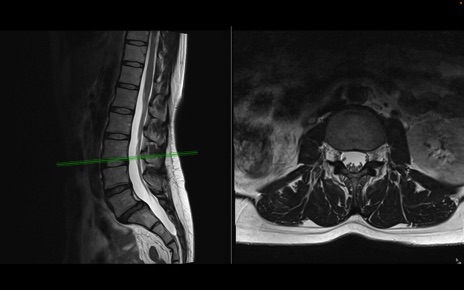

腰椎MRI

T2WI(横断像)

T2WI(矢状断像)